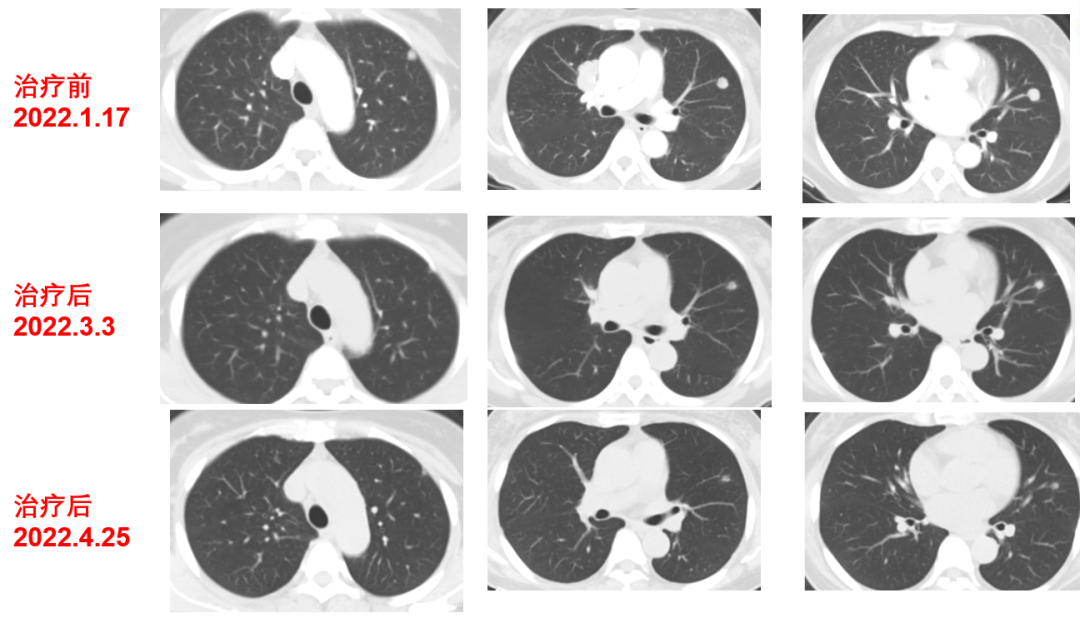

二线治疗(2021-12至2022-8-3,二线PFS:7月余):

于2021-12-03、2021-12-27给予伊尼妥单抗+吡咯替尼方案治疗2周期。2022.1.19始给予患者伊尼妥单抗+吡咯替尼+替雷利珠单抗治疗,两周期,四周期时的疗效评估可以看到,肺上病灶明显缩小,甚至有的病灶消失,肿瘤标志物也在持续下降。

肿瘤第二次进展(2022-8-3):在二线治疗7月余后,肿瘤标志物升高,CT也显示,肺上的病灶增大,患者双靶向+免疫治疗进展。